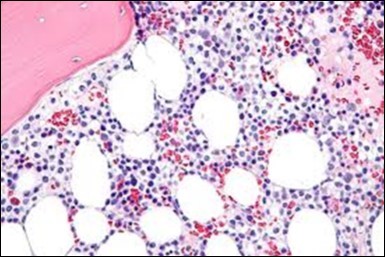

Figure 8.HCL: widely disseminated hairy cells within the bone marrow trabaculae(24).

HCL: widely disseminated hairy cells within the bone marrow trabaculae(24).